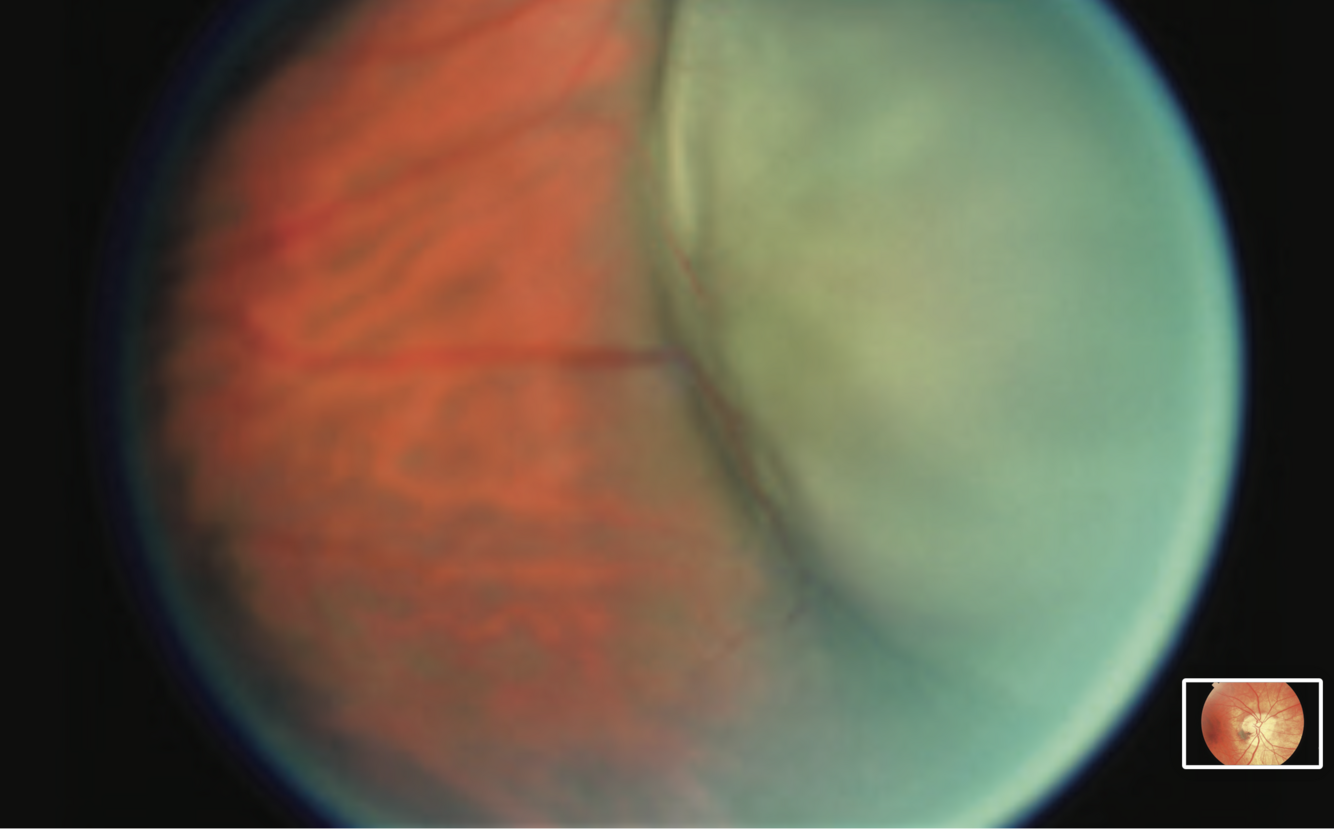

Retinal Detachment

- area of bullous retina showing area of elevation with fluid

- may see tear also